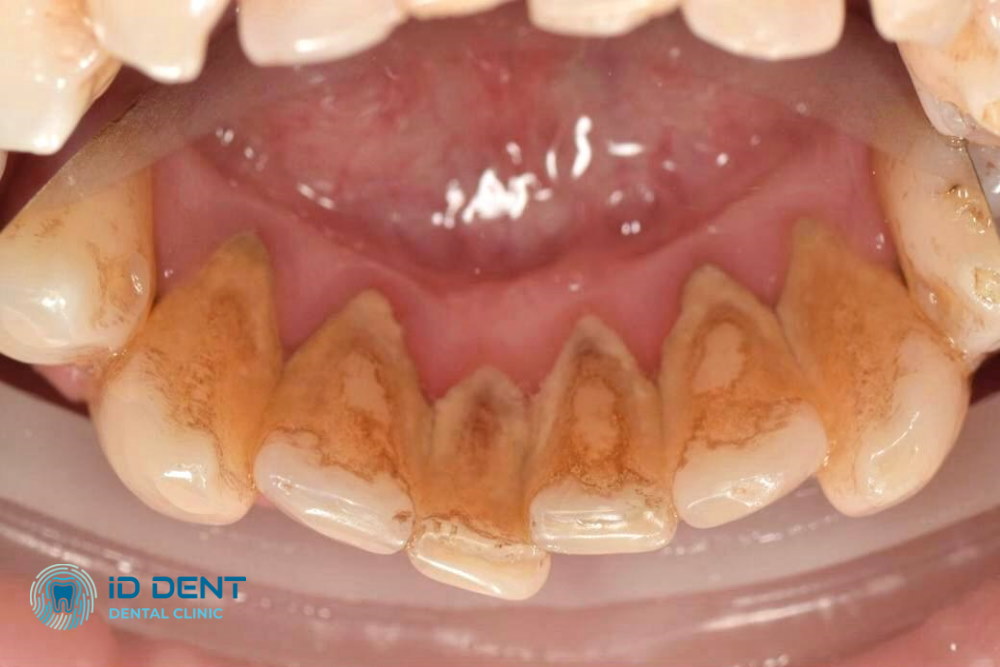

Antes

Antes Después

Después

El sarro es placa dental mineralizada que se forma en la superficie de los dientes. A menudo se visualiza como depósitos oscuros en la parte cervical de los dientes, lo que se explica porque está compuesto de restos de alimentos, células muertas, bacterias, sales de fósforo, hierro y calcio.